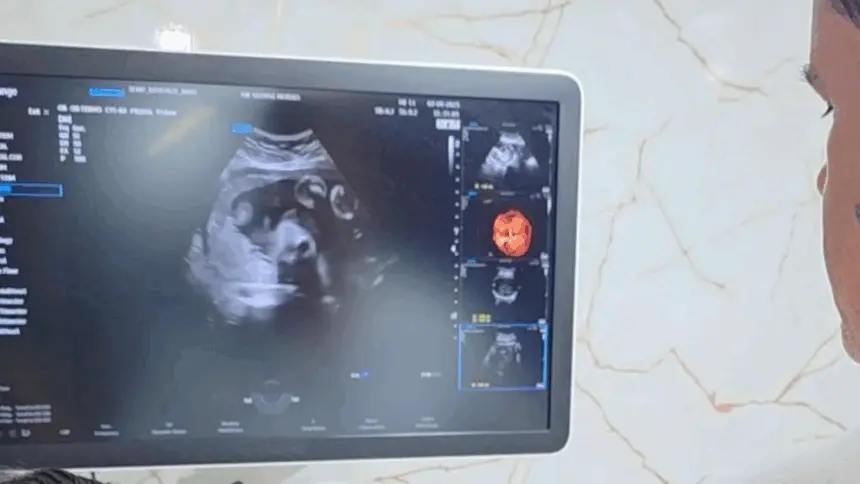

Os atendimentos acontecerão no Paço Municipal Laurentino Martins, na prefeitura, com distribuição de senhas a partir de 05h30 às 07h00 da manhã. Entre os exames oferecidos estão; ultrassonografia obstétrica, abdome superficial, abdome superior (com jejum de 12 horas), próstata (com bexiga cheia), endovaginal, bolsa escrotal, tireoide e mama. Cada paciente poderá realizar um exame.

A ação tem como objetivo ampliar o acesso da comunidade a serviços de diagnóstico por imagem, garantindo agilidade e qualidade no atendimento. O benefício se soma a outras medidas já implementadas pela Prefeitura de Goianésia para fortalecer a saúde preventiva no município.